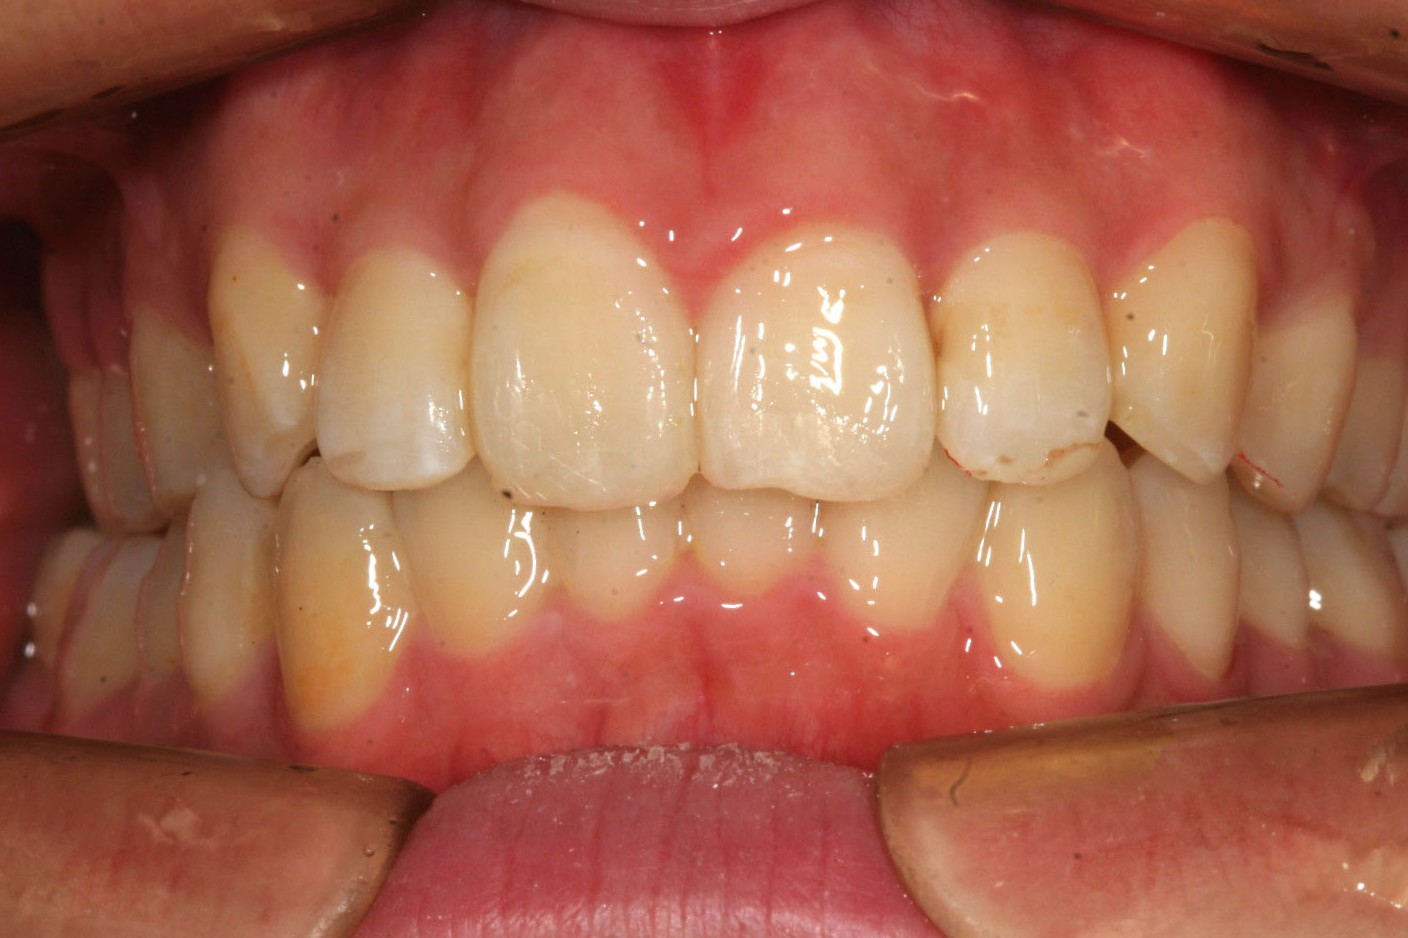

抜歯もせず綺麗なU字形に治りました。

下顎も綺麗に修正出来ました。

でっぱも改善出来ました。

今回の症例は稀にみる下顎のアーチフォームの乱れが激しく乱れていましたのでこれを修正するのに手間取りました。

多少下顎のアーチフォーム改善にワイヤーを使用しましたが、これだけ綺麗になれば患者様にも満足して頂けました。

気になる出っ歯観も改善しました。